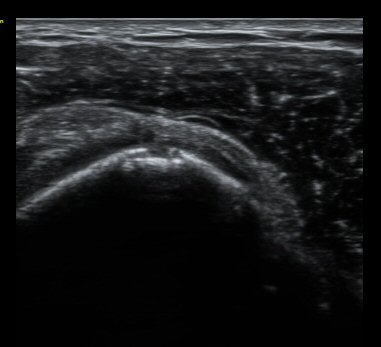

ȸÀü±Ù°³°£°Ý Ⱦ´Ü¸é°Ë»ç¿¡¼­ Á¡¾×³¶³» ¼ö¾×Àú·ù°¡ °üÂûµÈ´Ù(±×¸² 1). ÀÌµÎ¹Ú±Ù°Ç °í¶û¿¡¼­´Â ƯÀÌ ¼Ò°ßÀ» º¸ÀÌÁö ¾Ê´Â´Ù(±×¸² 2). ȸÀü±Ù°³°£°Ý ³»Ãø¿¡¼­ °ß°©ÇϱٰÇÀÇ ÆÄ¿­°ú Á¡¾×³¶³» ¼ö¾×Àú·ù°¡ °üÂûµÈ´Ù(±×¸² 3, 4). ±Ø»ó°Ç Ⱦ´Ü